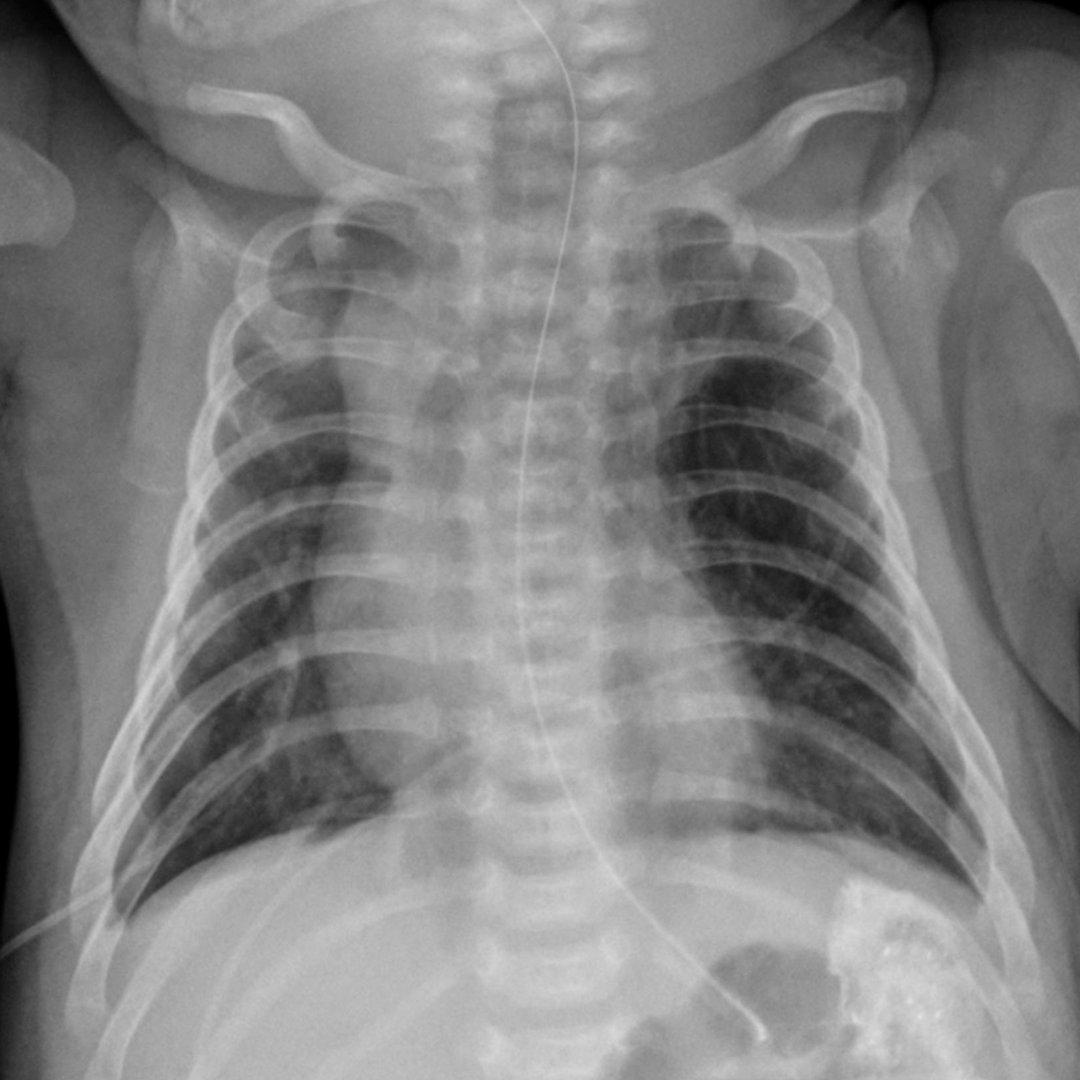

A 4-month-old boy presents to the hospital with worsening tachypnea. What does this chest radiograph tell you? http://bit.ly/2vjlvk2 pic.twitter.com/xTtHYB6iwB